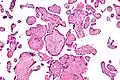

![]() صورة مجهرية لالتهاب الزُغابات مجهول السَبب، الصبغة المُستعملة هي صبغة الهيماتوكسيلين والإيوسين صورة مجهرية لالتهاب الزُغابات مجهول السَبب، الصبغة المُستعملة هي صبغة الهيماتوكسيلين والإيوسين | |

حَسب علم أمراض الانسجة فَإنَّ التهاب الزُغابات مجهول السَبب يتميز بارتشاح لمفاوي مجهول السَبب، وَيتميز بعدم تواجد الخلايا البلازمية، حيثُ أنَّ وجود الخلايا البلازمية أثناء الالتهاب يُدل على أنَّ سَبب الالتهاب هوَ العدوى، مِثل العدوى بالفيروس مضخم الخلايا.

التهاب الزغابات مجهول السبب (تكبير مُتوسط)